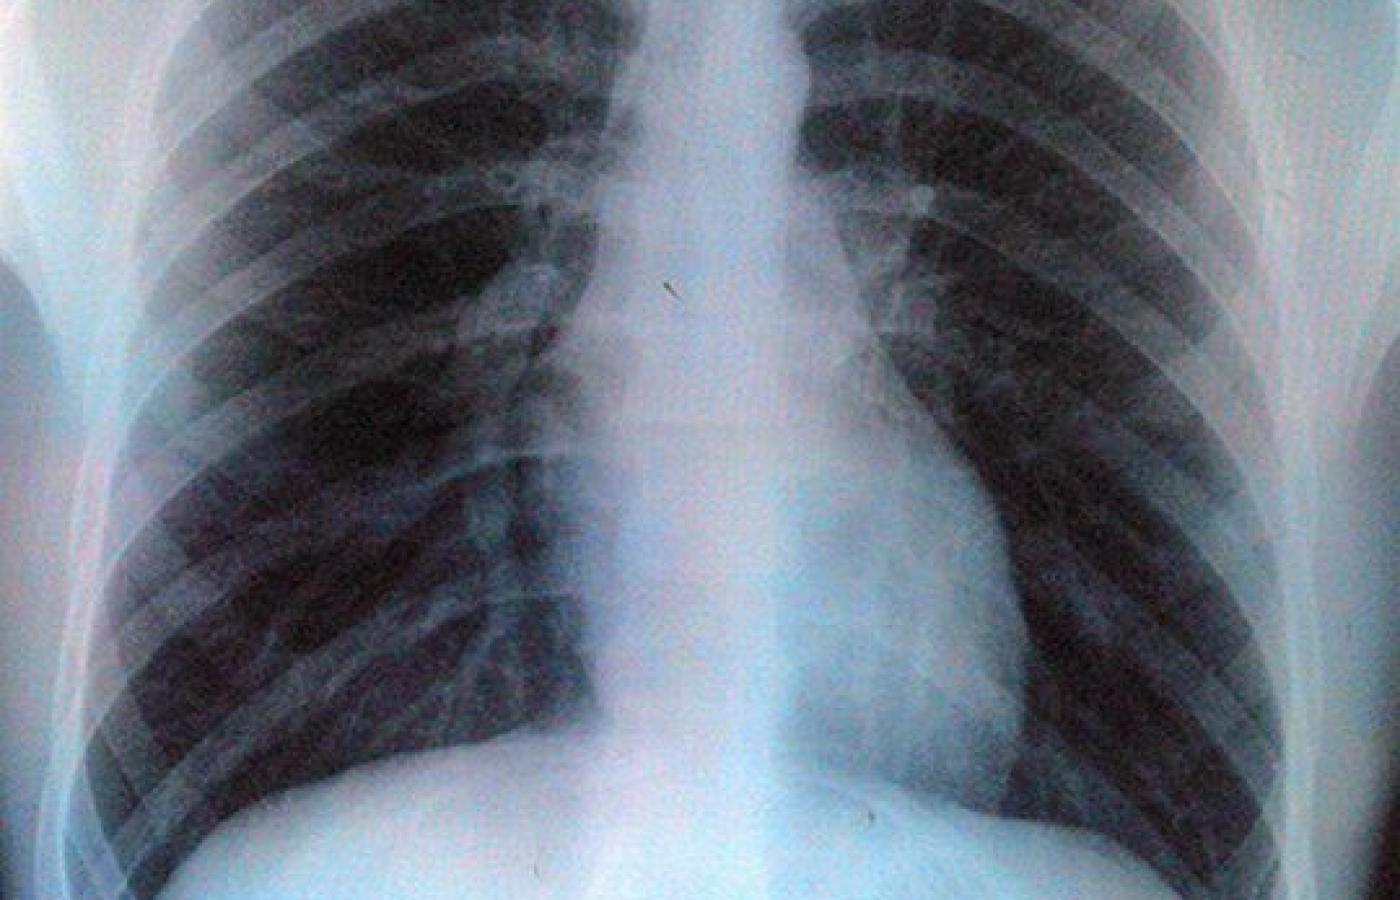

Gruźlica, która wydawała się chorobą zaleczoną, znów jest bardzo groźna Gruźlica, która wydawała się chorobą zaleczoną, znów jest bardzo groźna Aidan Jones / Flickr CC by SA

Gruźlica zabija rocznie 1,7 mln ludzi na świecie. Pilnie potrzeba nowych leków. Ale wielkie koncerny nie są nimi zainteresowane. Indie znalazły na to lekarstwo.

Krajem boleśnie dotkniętym tą logiką są Indie, na gruźlicę umiera tam dziennie około tysiąca osób. Umierają, bo drobnoustrój wywołujący chorobę Mycobacterium tuberculosis uodpornił się na dotychczas stosowane leki, a od lat 60. ubiegłego wieku nie pojawiła się praktycznie żadna nowa skuteczniejsza substancja lecznicza. Szansą na poprawę sytuacji stało się ogłoszenie w 1998 r. sekwencji genomu Mtb. Znając informacje o strukturze genetycznej chorobotwórczego organizmu, można dociekać molekularnych mechanizmów wywołujących infekcję i na tej podstawie projektować nowe leki. Nie wystarczy jednak do tego sama sekwencja genomu, potrzebna jest dokładna mapa oddziaływań między poszczególnymi genami a kodowanymi przez nie białkami.